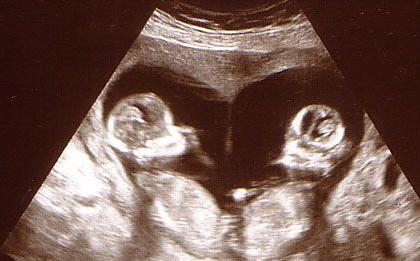

A few weeks later, Zara was amazed to discover SHE WAS HAVING TWINS! She established prenatal care

Zara had two ultrasound appointments at Resource Health. She leaned in during the scans but continued to express her feeling that she couldn’t have a baby with a man who wasn’t her partner. Anita, the nurse performing the scans, encouraged Zara to take as much time as she needed to think through her decision and how it could look long term.

When Zara came in for a third ultrasound, she was still undecided and told Anita she tried not to think about the pregnancy when she wasn’t at one of her appointments. During the scan that day, Zara saw her baby for the first time. As tears filled Zara’s eyes, Anita asked if she could pray for her.

Zara came in for a fourth scan and asked to take pictures of her baby home with her. She was surprised to see her baby moving this time! We showed her fetal models when she asked about her baby’s development. This conversation allowed us to discuss things like taking prenatal vitamins, setting up Medicaid, and seeing an OB/GYN.